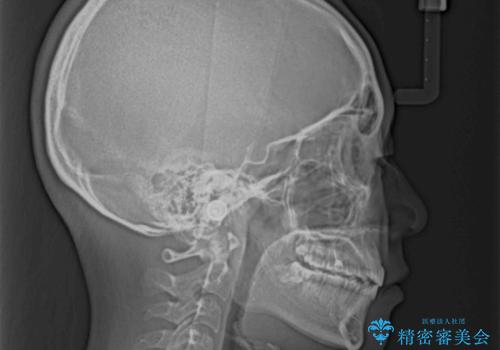

当初は八重歯やデコボコが一番気になっていましたが、抜歯矯正により口元の突出感が改善されるにつれ、口の閉じやすさを実感するようになってきました。

部活動で調整来院に来られないことがしばしばあり、期間は予定よりもかかりましたが、きれいに仕上げることができました。